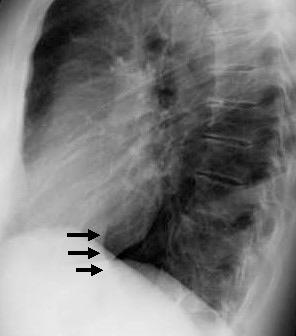

Accidente de tráfico

Rx: Niveles hidroaéreos en hemitórax izquierdo Desviación mediastínica Ausencia de intestino en abdomen. Configuración en reloj de arena del intestino herniado “Tubo nasogástrico”

Furak J et al. Diaphragm and transdiaphragmatic injuries. J Thorac Dis 2019